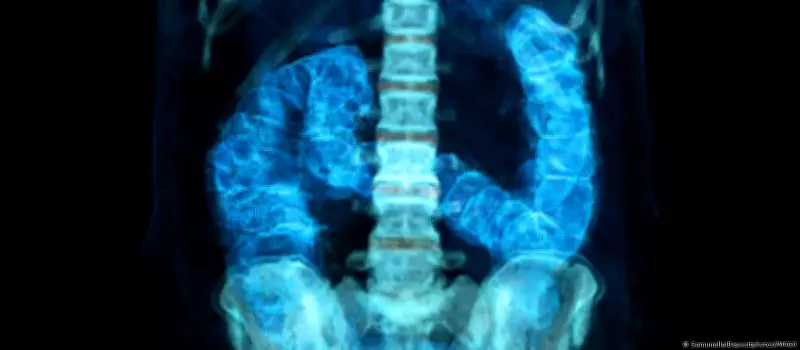

Câncer colorretal avança entre jovens: mortes devem crescer 36% no Brasil até 2040

O câncer colorretal, tradicionalmente associado a adultos mais velhos, está apresentando um crescimento alarmante entre pessoas com menos de 50 anos. Nos Estados Unidos, essa neoplasia já se tornou a principal causa de morte por câncer nessa faixa etária, enquanto no Brasil as projeções indicam um aumento de 36% nas mortes relacionadas à doença até 2040.